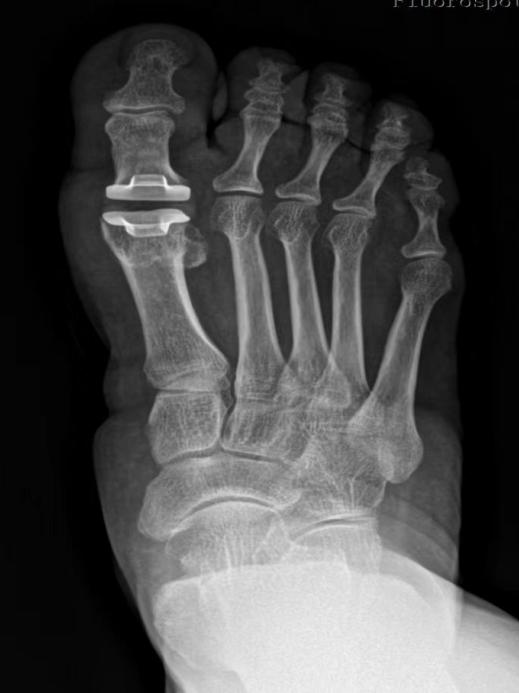

术前DR 术后DR

创伤骨科团队制定了周密的手术方案,在麻醉科、手术室的配合下,在南方医科大学第三附属医院足踝外科曾参军主任的指导下,创伤骨科主任房辉强带领副主任医师万富贵、副主任医师欧阳玉斌、主治医师张鹏为石阿姨行人工跖趾关节全关节置换术。手术顺利完成,患者术后恢复良好,效果满意。

房辉强指出,随着生活质量的提高,人们对足踝部健康越来越重视。拇僵硬是以第一跖趾关节疼痛和活动受限为特征的关节退行性病变。早期症状主要包括疼痛、肿胀和跖趾关节滑膜炎,背伸受限则是其中最典型的特征之一。此类患者常诉步态僵硬,第一跖趾关节局部疼痛,在步行和站立时加重,休息后缓解。临床上常采用关节唇切除术、关节成形术、第一跖骨截骨术、跖趾关节融合术等,但这些传统术式在解决拇僵硬引起疼痛的同时,一定程度上牺牲了正常跖趾关节的功能活动。近年来,我国逐渐采用人工生物金属聚乙烯假体全关节置换术,很多足踝关节疾病在保守治疗无效的情况下均可采取小关节置换,此类手术创伤小、并发症少、既缓解疼痛又保留正常功能。